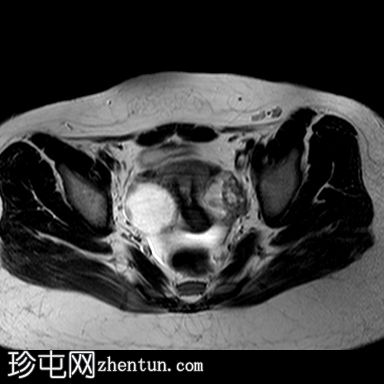

MRI

矢状位

T2加权像

阴道明显扩张,T1加权像呈中高信号,T2加权像呈高信号,耻骨联合下方可见一小局灶性隆起。

子宫大小正常,分区解剖结构正常。宫颈MRI表现正常。

右侧卵巢可见一圆形、边界清晰的囊肿,最大轴位径为4.2 x 4.3 cm,T1加权像呈低信号,T2加权像呈高信号。

左侧卵巢大小正常,可见一小出血性囊肿。

盆腔内可见少量游离液体。